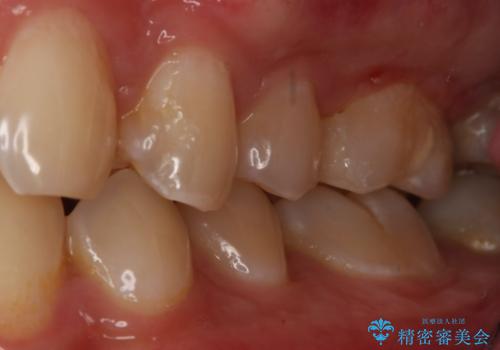

- 左上6番の銀歯のやり変えを希望し来院された患者様です。

切削量・形態を考慮し、セラミックインレーでの治療を計画しました。

銀歯直下のう蝕が深かったのでCRで裏層した上で形成、印象をしています。